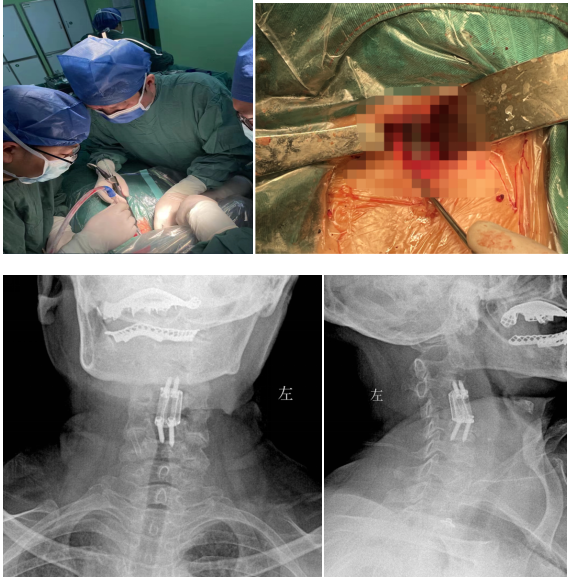

經(jīng)過多學科會診(MDT),完善術(shù)前相關(guān)準備后,由蘇光輝主任主刀,帶領(lǐng)團隊錢軍、鄧三東等,精準完成病灶清除、椎管減壓、植入3D打印cage等流程,在麻醉師、手術(shù)室的全力配合下,整臺手術(shù)一氣呵成,手術(shù)順利。

經(jīng)過周密細致的術(shù)前討論,脊柱外科團隊最終決定為該患者擬行頸椎病灶清除、椎管減壓+植骨融合術(shù),考慮患者高齡,又有骨質(zhì)疏松,為更好保障重建穩(wěn)定性,采用3D打印進行術(shù)前規(guī)劃設計假體進行植入,此款融合器是國內(nèi)首款SLM激光打印融合器,具有解剖匹配、骨融合確切等優(yōu)勢,為取得優(yōu)良手術(shù)效果打下了堅實基礎。